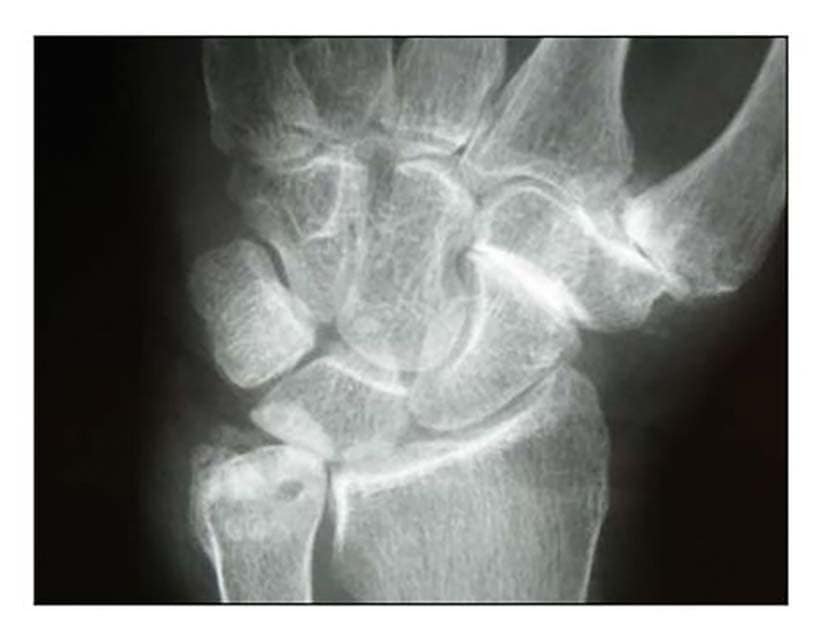

Die Rhizarthrose gehört zum rheumatischen Formenkreis und macht sich je nach Stadium durch eine sehr schmerzhafte zunehmende arthrotische Zerstörung des Daumensattelgelenkes bemerkbar. Nach einer Untersuchung von Pellegrini 1 erkranken Frauen 10- bis 15-mal häufiger an Rhizarthrose als Männer. Das deckt sich mit den Erfahrungen des Autors aus den Evaluierungsübersichten von fast 4.000 Patientinnen und Patienten mit dem durchschnittlichen Verhältnis von 13:1 zugunsten der Patientinnen. Die Rhizarthrose tritt bei Frauen nach den Erfahrungen des Autors ca. 3 Jahre nach dem Beginn der Menopause auf und ist vermutlich genetisch bedingt: Nur zwei Prozent der Patientinnen des Autors erwähnten in der Anamnese, keine Schwangerschaft gehabt zu haben. Auslöser für die Rhizarthrose bei Männern ist in den meisten Fällen eine traumatisch bedingte Verletzung des Daumensattelgelenkes („Skidaumen“) oder eine ständige berufliche Überbeanspruchung, zum Beispiel bei Vibrationen durch Maschinen oder auch durch handschriftliches Schreiben in Büroberufen. Die Rhizarthrose tritt nach Eaton/Littler radiologisch klassifiziert in vier Stadien auf (Abb. 1) 2:

- Stadium I: normale Gelenkkonturen, erweiterter Gelenkspalt (Erguss)

- Stadium II: geringe Gelenkspaltverschmälerung, evtl. vorhandene Gelenktrümmer kleiner als 2 mm

- Stadium III: sklerotische und zystische Veränderungen im subchondralen Knochen, Osteophyten größer als 2 mm, Zerstörung des Daumensattelgelenkes, normale trapezioskaphoidale Gelenkfläche

- Stadium IV: zusätzlich zum Verschleiß der trapeziometakarpalen Gelenkfläche degenerative Veränderungen im Bereich der trapezioskaphoidalen Gelenkfläche

Die Patienten geben bereits beim Stadium I Schmerzen beim Pinzettengriff und/oder beim kleinen oder großen Rundgriff an. Häufig treten die ersten Schmerzen beim Schwenken der Daumen zur volaren Handfläche auf. Beim Stadium II treten die Subluxationsstellung im Daumensattelgelenk und eine temporäre Schmerzhaftigkeit bei vielen Tätigkeiten sowie häufig auch in Ruhe auf. Im Stadium III findet sich eine deutliche Luxierung des Daumensattelgelenkes und eine beginnende Proximalisierung des Mittelhandknochens des Daumens. Zusätzlich geben die Patientinnen und Patienten eine Schmerzhaftigkeit auch bei bereits geringen Bewegungen an. Häufig wird auch über Nachtschlafstörungen beim Greifen nach dem Kopfkissen oder dem Oberbett geklagt. Im Stadium IV finden sich ebenfalls eine deutliche Luxierung des Daumensattelgelenkes, eine deutliche Proximalisierung des Daumenmittelhandknochens und eine Schmerzhaftigkeit auch bei bereits geringen Bewegungen. Häufig findet man eine Fehlstellung des Daumens im Daumengrundgelenk. Oft ist zunächst die sekundäre Hand – beim Rechtshänder das linke Daumensattelgelenk, beim Linkshänder umgekehrt – von der Rhizarthrose betroffen. 18 Prozent der versorgten Patienten litten an einer zu versorgenden doppelseitigen Rhizarthrose. Durch einen vom Autor 2010 entwickelten Testgriff – ähnlich dem Ansatz des Daumens beim Händeschütteln – durch Druck des Daumens der Patienten in die Tabatiere des Behandlers kann festgestellt werden, bei welchem Druck der Schmerz einsetzt.